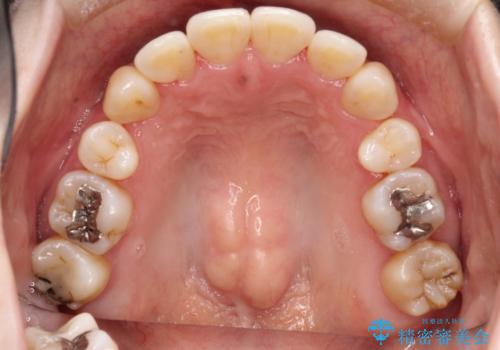

コンプレックスだった前歯のガタガタがここまで綺麗になるなんて!!

初診時の歯並びの状態としては、上下に強いガタガタがある状態であり、それが原因で口腔内の清掃状態も極めて悪い状況でした。

抜歯によるスペースを利用し、強いがたつきの改善を行いました。

治療に関して期間こそかかってしまったものの、見た目、嚙み合わせ及び、治療期間や施術内容に大変ご満足いただきました。